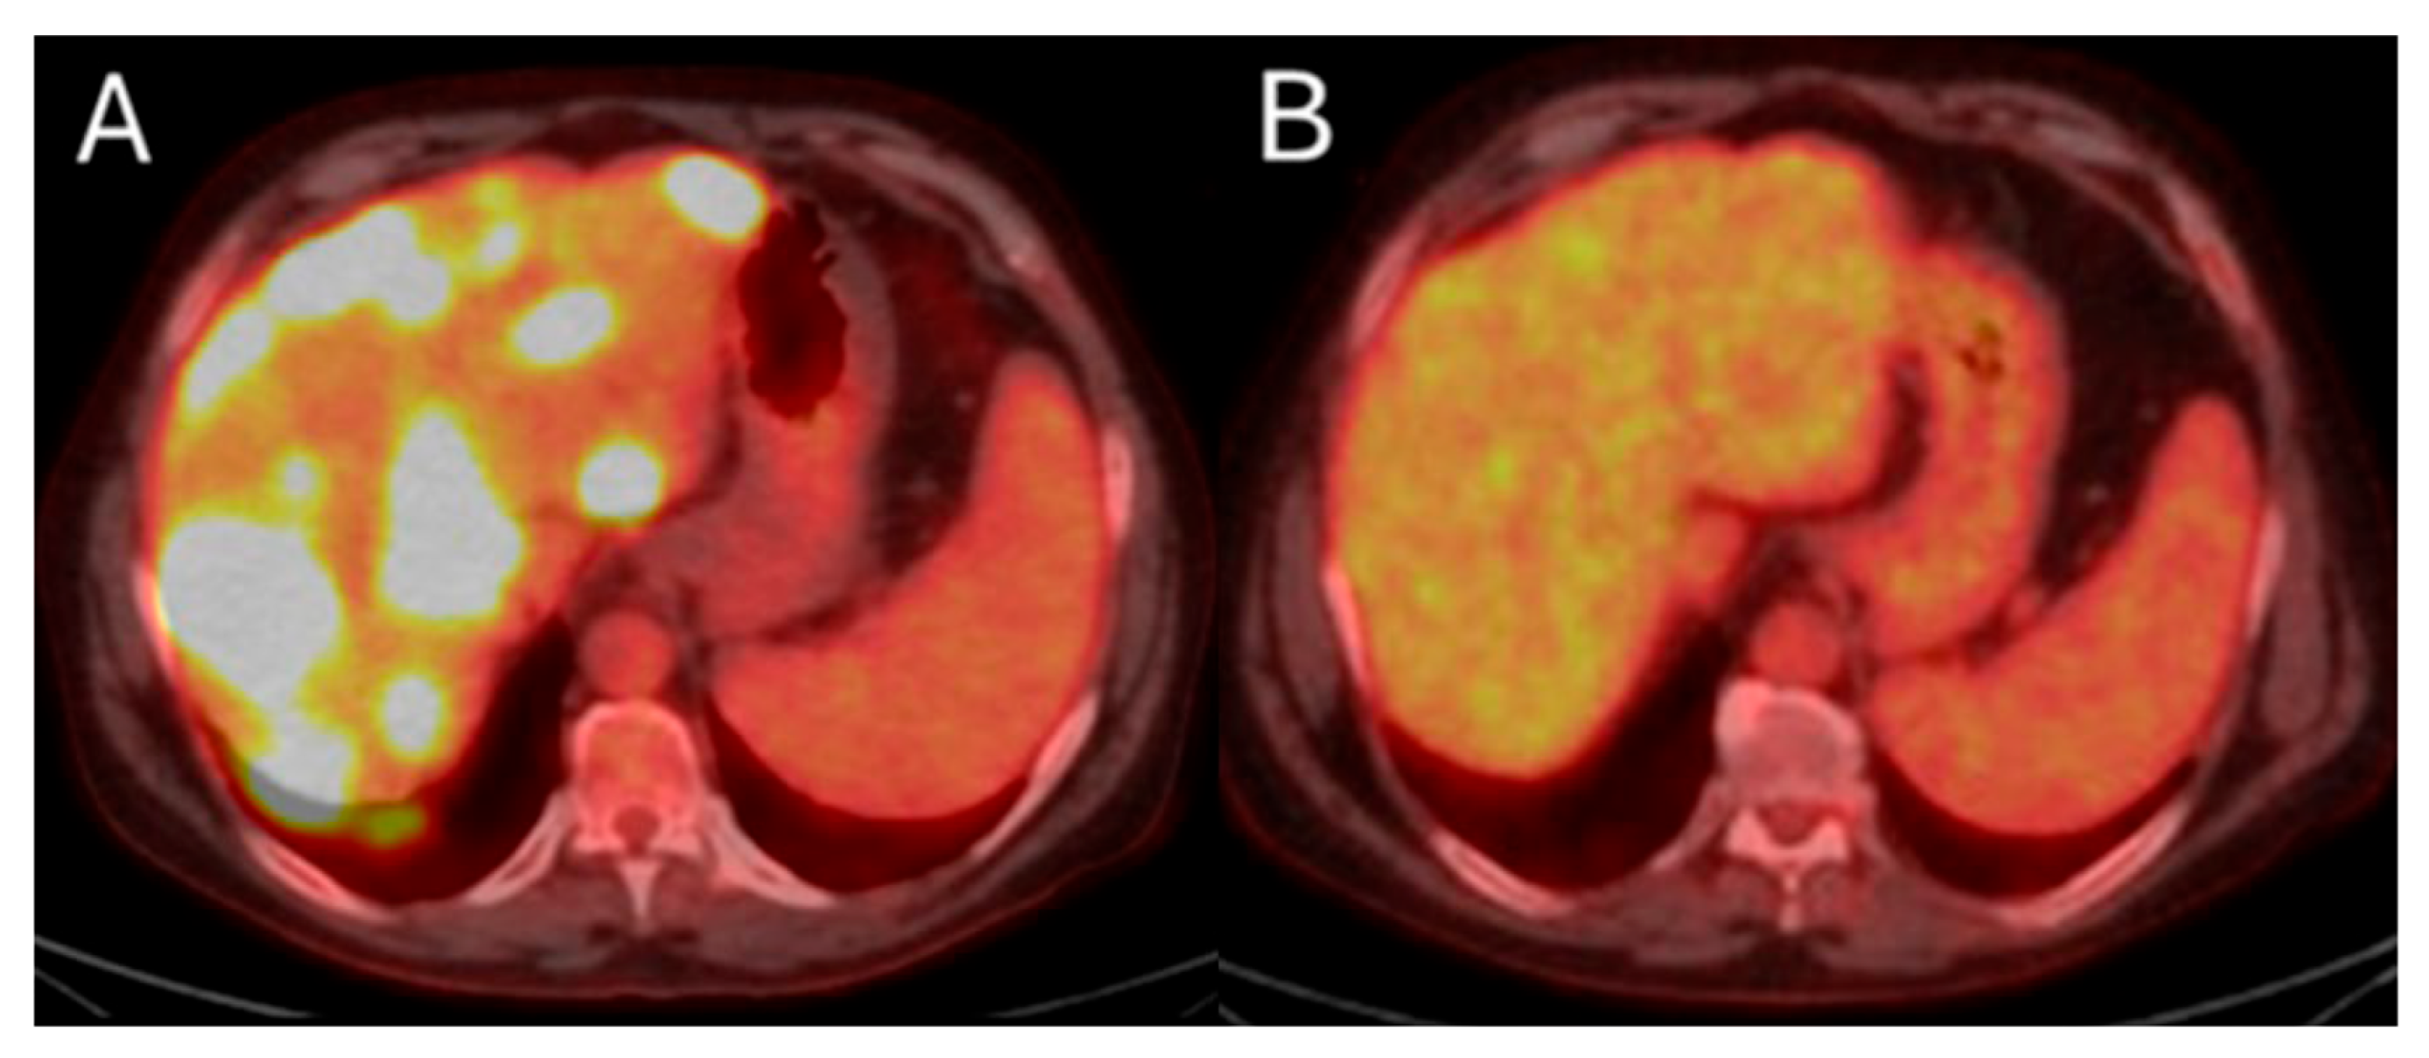

There are different methods used to calculate the 90Y administration dose. The initially reported method of dosimetry was utilizing the Body Surface Area (BSA) model. This technique, commonly used for SIR-spheres, calculates the prescribed dose using the BSA and the tumor burden within the target liver parenchyma [163,164]. In an effort to increase the ability of operators to provide personalized dosimetry based on tumor characteristics and therapeutic intent, a small patient trial of 15 patients using Tc99-MAA for LSF calculation, CT to calculate liver volume, and post-TARE bremsstrahlung scan for actual 90Y delivery location confirmation, generating the Medical Internal Radiation Dose (MIRD) model [165]. MIRD utilization is recommended by Thera-sphere manufacturers and was also used in the EPOCH trial. Main limitation derives from the fact that it is a single-compartment model, which contains both the target tumor and surrounding healthy parenchyma (Figure 6). Dose volume histogram (DVH) curves that display the dose distribution within the different generated compartments and the included structures and tumor (Figure 7).

Figure 6.

86-year-old with synchronous relatively large metastasis in the right lobe on pre-treatment ceCT (A) undergoes radiation segmentectomy. Post-TARE Medical Internal Radiation Dose (MIRD) dosimetry is demonstrated according to the workflow using MIM DEV software version 3.3.7 using the post-TARE bremsstrahlung scan (B–D). The contours of the treated tumor are illustrated by the red line; yellow circle represents the 5 mm margins, and the green circle represents the 10 mm margins around the target tumor (B). The area defined by the brown circular line represents the single compartment used by the MIRD method that contains the target tumor (C). The area enclosed by the blue line represents the non-tumor liver parenchyma (D).

Figure 7.

Same patient of Figure 6. Post-TARE MIRD dosimetry Dose Volume Histogram (DVH) curve (% volume coverage ~ actual dose delivered) with utilization of MIM software version 3.3.7. DVH demonstrates dose distribution at the target tumor (red color), at the 5 mm margins (yellow color) and 10 mm margins (green color) around the tumor, at the liver single compartment created by the software that contains the target tumor (brown color), and at the non-tumor liver parenchyma (blue color).